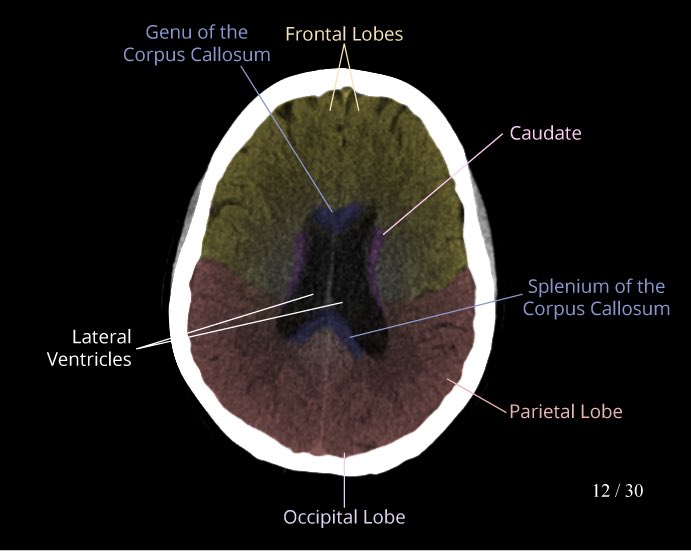

نبدأ بأشعة مقطعية طبيعية للرأس

Normal head CT scan

Non contrast

صور جدا مفيدة للاناتومي: 👇🏻